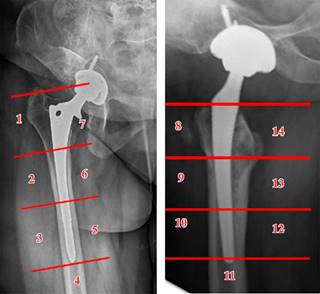

Radiológicos: hallazgo en radiografías simples de radiolucencias progresivas de más de 2 mm en dos radiografías espaciadas al menos un año (describiendo su localización según las zonas de Gruen) (Figura 2). También se tuvieron en cuenta otros hallazgos radiológicos como el stress shielding, el fenómeno del pedestal, el desgaste del polietileno o el hundimiento del vástago. Por último, también incluimos pacientes con hallazgos incongruentes en radiografías simples, pero que mostraron signos de aflojamiento en otras pruebas complementarias radiológicas (resonancia magnética, tomografía computarizada y gammagrafía).

En relación con los parámetros radiológicos de aflojamiento, no se encontró que el número de zonas de Gruen afectas o que la suma en milímetros de las dimensiones de las zonas aflojadas mostrara diferencias estadísticamente significativas entre los dos grupos (p = 0.429 y p = 0.524 respectivamente). Sí se apreció una mayor afectación del área 7 de Gruen en el grupo control (78.9%) que en los casos (22.2%) (p = 0.01). Otras tendencias relevantes sin significación incluyen que el aflojamiento en zona 1 fue más frecuente en fracturas AG de Vancouver, el aflojamiento en zona 2 se produjo frecuentemente en fracturas tipo B2 (Figura 3).

Figura 5: Hundimiento del vástago, medido empleando como referencia distancia entre el hombro de la prótesis y la punta del trocánter mayor.